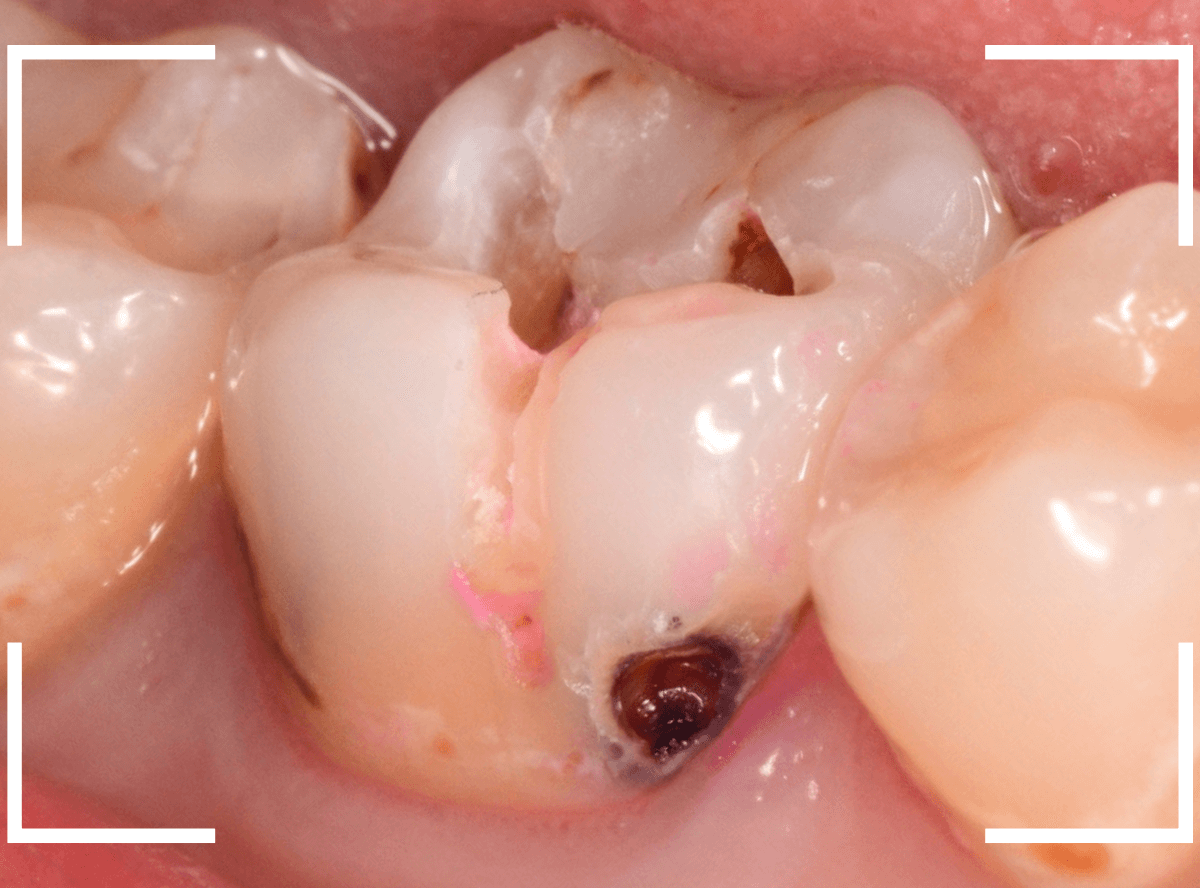

こちらも、虫歯が歯のあちこちで進行してしまっている患者さんのケースです。

特に側面の虫歯が深そうです。

側面にできた虫歯はレントゲン写真では診断しづらくやっかいです。

今回は「見るからに深そう」ですが。

さすがにレントゲン写真でも虫歯がありそうな事は確認できますが、実際にどうなってるのかはあまりはっきりわかりません。

少しずつ虫歯を除去していきます。

歯の側面から、手前の歯までつながった虫歯になっていました。

手前の歯までの虫歯を除去しました。

歯の後ろ側の側面も、大きな虫歯になっていますので、処置します。

隣の歯との間(隣接面)は、中で虫歯が広く進んでることが多いです。

結局、前後の歯に渡る広い虫歯でした。

レントゲン写真だけでは、ここまでの虫歯は判断できませんでした。